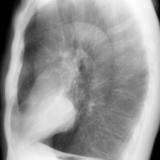

Case 1 Lat

Date: 03/17/2004

Views: 2983